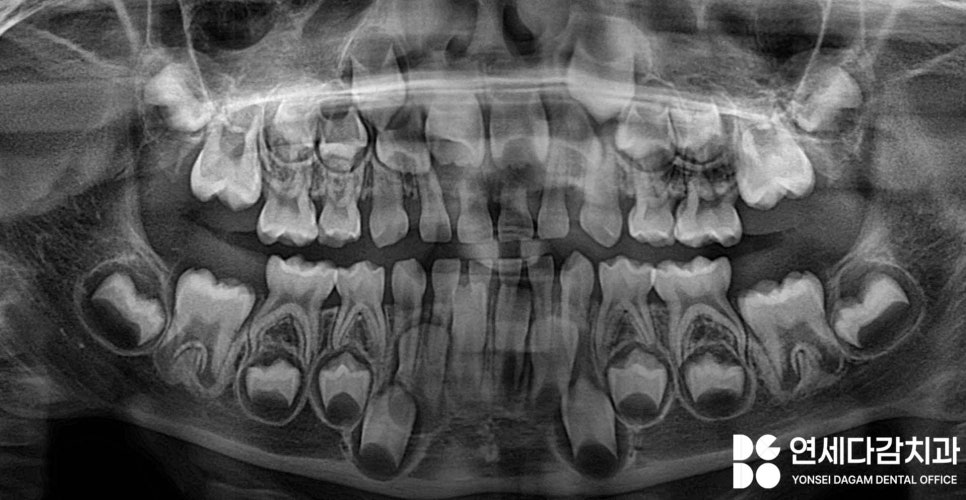

위 앞니 잇몸이 부어있는 것이 발견되었으나

치아의 흔들림은 관찰되지 않습니다.

다행히 치아에도 특별한

외상은 없고,

엑스레이 상 문제 삼을 소견이 아직은

보이지 않을 경우에는

별 다른 치료를 시행하지 않고

우선 지켜보게 됩니다.